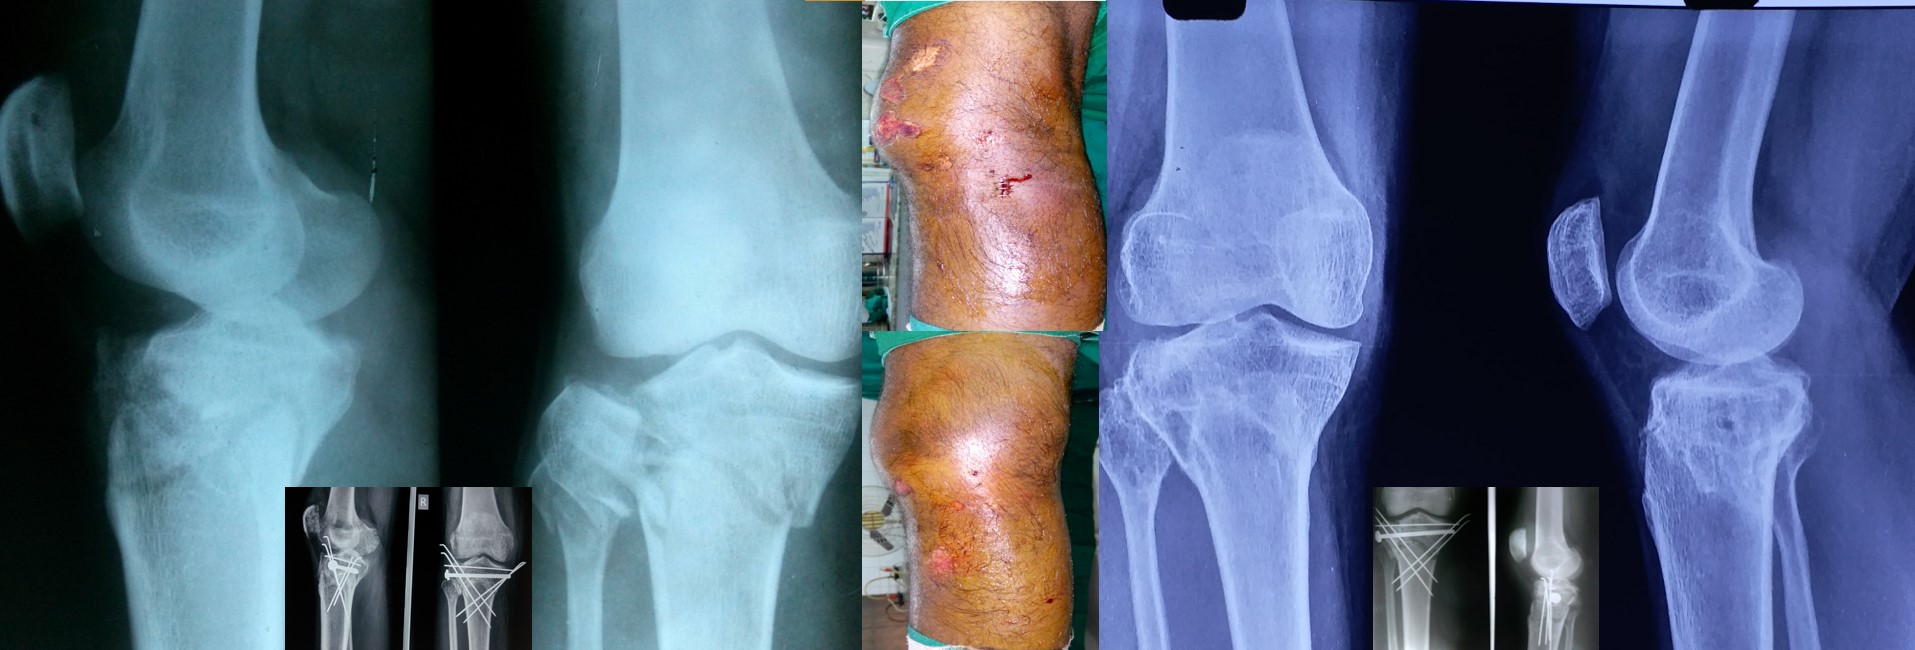

CRPP ( Closed Reduction Percutaneous Pinning )

• CRPP is a minimally invasive surgical procedure under regional anesthesia and the patient can be discharged on the 2nd postoperative day.

• No skin incision is required, and fracture heals faster than open surgeries as there is no iatrogenic soft tissue damage or disturbance to the fracture hematoma.

• No implants projecting outside the skin and hence painless adjacent joint movement is possible immediately after CRPP.

• Most of the metaphyseal fractures of both upper and lower limbs can be successfully treated by CRPP.

• It can be applied safely in fractures, where ORIF (Open Reduction Internal Fixation ) cannot be performed or postponed due to impending soft tissue complications.